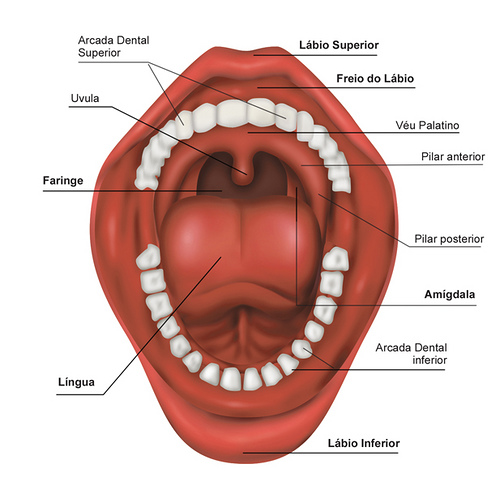

A cavidade oral compreende os dois terços anteriores da língua, as gengivas, a superfície interna das bochechas e lábios, a parte inferior da boca abaixo da língua (o assoalho oral), parte superior do osso da boca (o palato duro) e a área atrás dos dentes (o trígono retromolar).

O câncer, ou cancro, de boca aparece com a presença de um tumor maligno que pode afetar qualquer parte da cavidade oral: gengiva, língua, mucosa interna das bochechas, palato, lábios, glândulas salivares e assoalho oral.